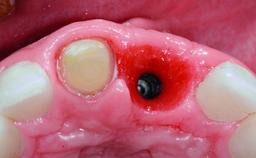

A 32-year-old female Caucasian patient with a compromised maxillary right central incisor was referred to us by a general dentist. Her chief complaints were discomfort and mobility of tooth 11 with unsatisfactory esthetics due to discoloration. The patient reported a previous trauma, some years earlier, as the origin of pathology on the afflicted tooth. Anamnesis was negative for any other dental or periodontal pathology in the remaining dentition. The patient did not take any medication and reported to be a light smoker (5–10 cigs/day). She had high esthetic expectations of her treatment. The extraoral examination revealed a high smile line with full exposure of her maxillary teeth and surrounding soft tissue in the area between the second premolars.

Bone Augmentation Horizontal|Simultaneous|Staged

Augmentation Materials Autogenous chips|Xenogenous|Membrane

Bone Volume Deficient horizontally, requiring prior grafting